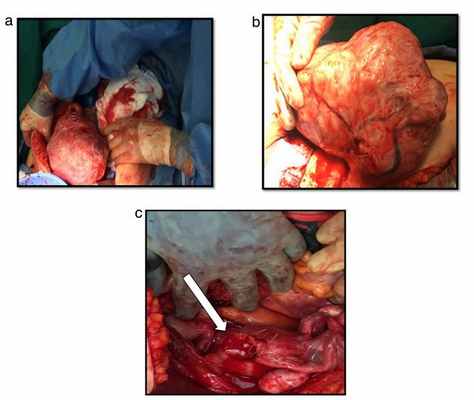

В данном случае рассмотрим конкретный пример полностью вывернутой шейки матки из-за выпавшей огромной лейомиомы шейки матки, имитирующей хроническую послеродовую инверсию матки у женщин в перименопаузе.

52-летняя женщина в перименопаузе поступила в нашу клинику с изъязвленным, некротическим, инфицированным и опухшей выпавштим образованием, происходящим из влагалища.

Беременности – 4, родов – 3, аборт – 1.

Из анамнеза: диагностирована миома матки 5 см в диаметре 2 года назад. Было предложено оперативное лечение, от которого она отказалась.

За 6 месяцев до описанный событий отметила появление образования из влагалища. За медицинской помощью так же не обращалась. На настоящий момент обратилась в больницу в связи с появлением изъязвлений на образовании, некупируемого болевого синдрома. Пациентке была выполненена гистерэктомия вагинальным доступом. Окончательный диагноз был поставлен уже интраоперационно.

а) некротизированный миоматозный узел

б) вывернутая шейка матки

а) матка

б) область наружного зева шейки матки

в) перевернутая шейка матки

г) лейомиома